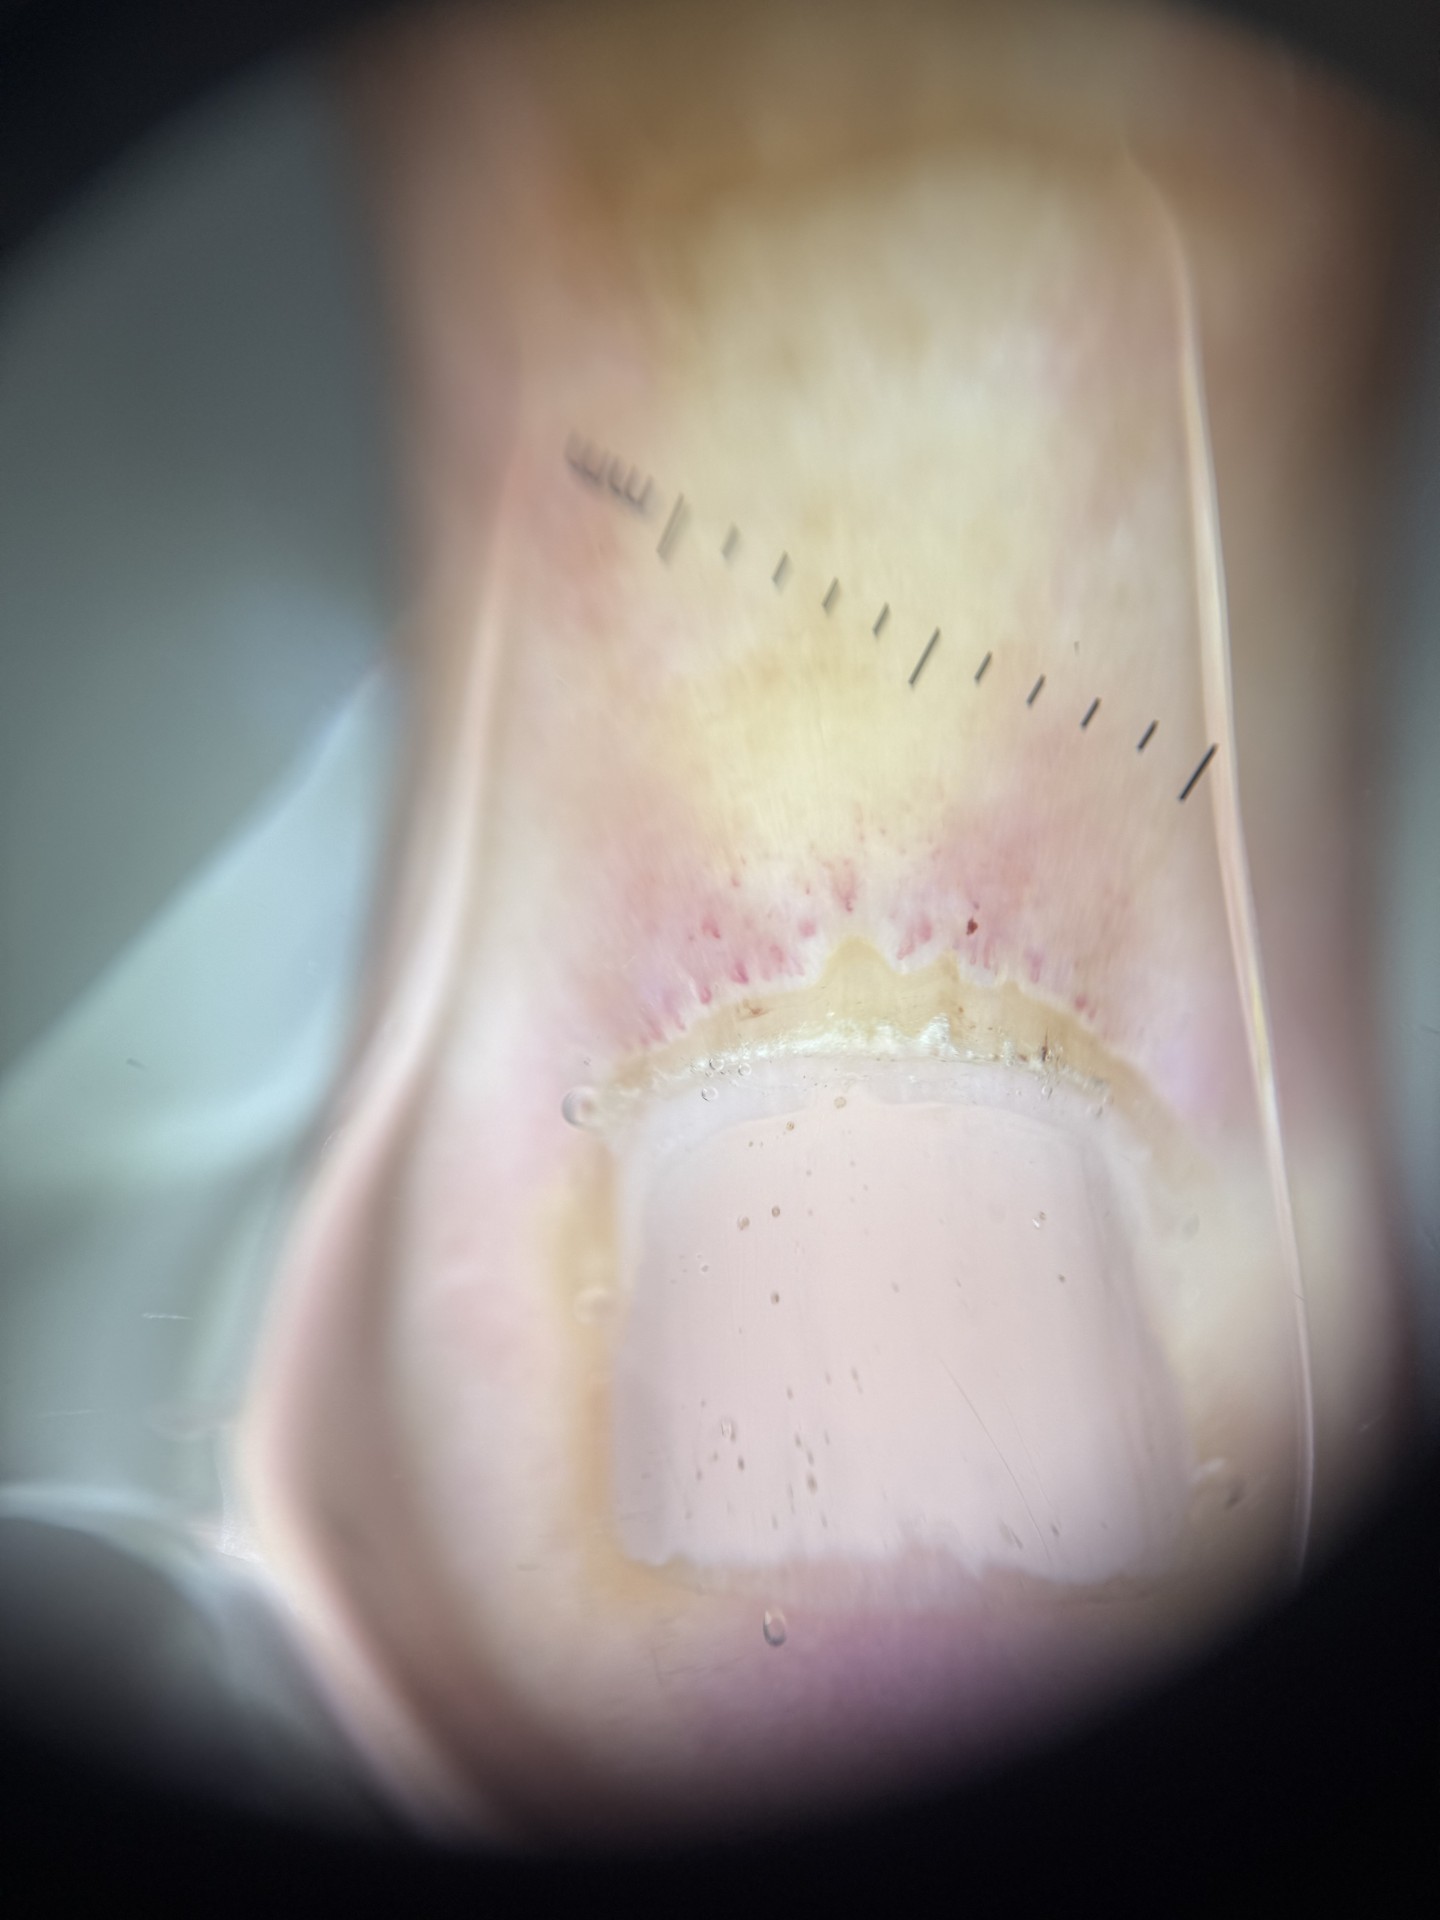

Paciente de 55 anos apresentando poiquilodermia em colo e dorso superior, pápulas eritematosas na face dorsal de todas as articulações interfalangeanas proximais das mãos e eritema periungueal em todas as unhas das mãos, além de cutículas irregulares. Ao fazer a dermatoscopia da região da prega ungueal, observou-se capilares alongados, capilares ramificados espessos, capilares dilatados gigantes, micro hemorragias e cutículas irregulares (Figura).

Na clínica da região periungueal em paciente com dermatomiosite pode-se ter cutículas irregulares, eritema, telangiectasias visíveis a olho nu, erosões, ulcerações ou atrofia da pele. Na sua dermatoscopia, por sua vez, desorganização da arquitetura capilar normal (sinal precoce), capilares dilatados gigantes, micro hemorragias, áreas avasculares, capilares ramificados espessos (mais específico de dermatomiosite), capilares alongados e capilares tortuosos.